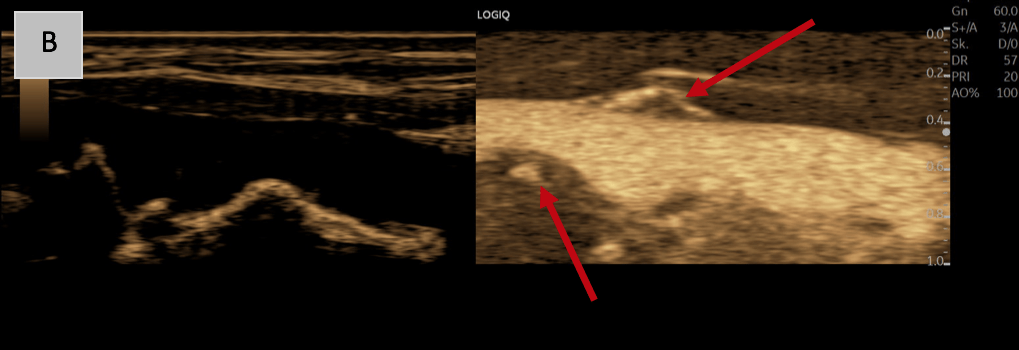

B: B-Mode in sepia and high-resolution flow imaging (B-Flow) along the longitudinal axis of the vessel reveals ulcerated plaque formations with notches and vasa vasorum showing transmural vascular ingrowth into the plaque (red arrow).